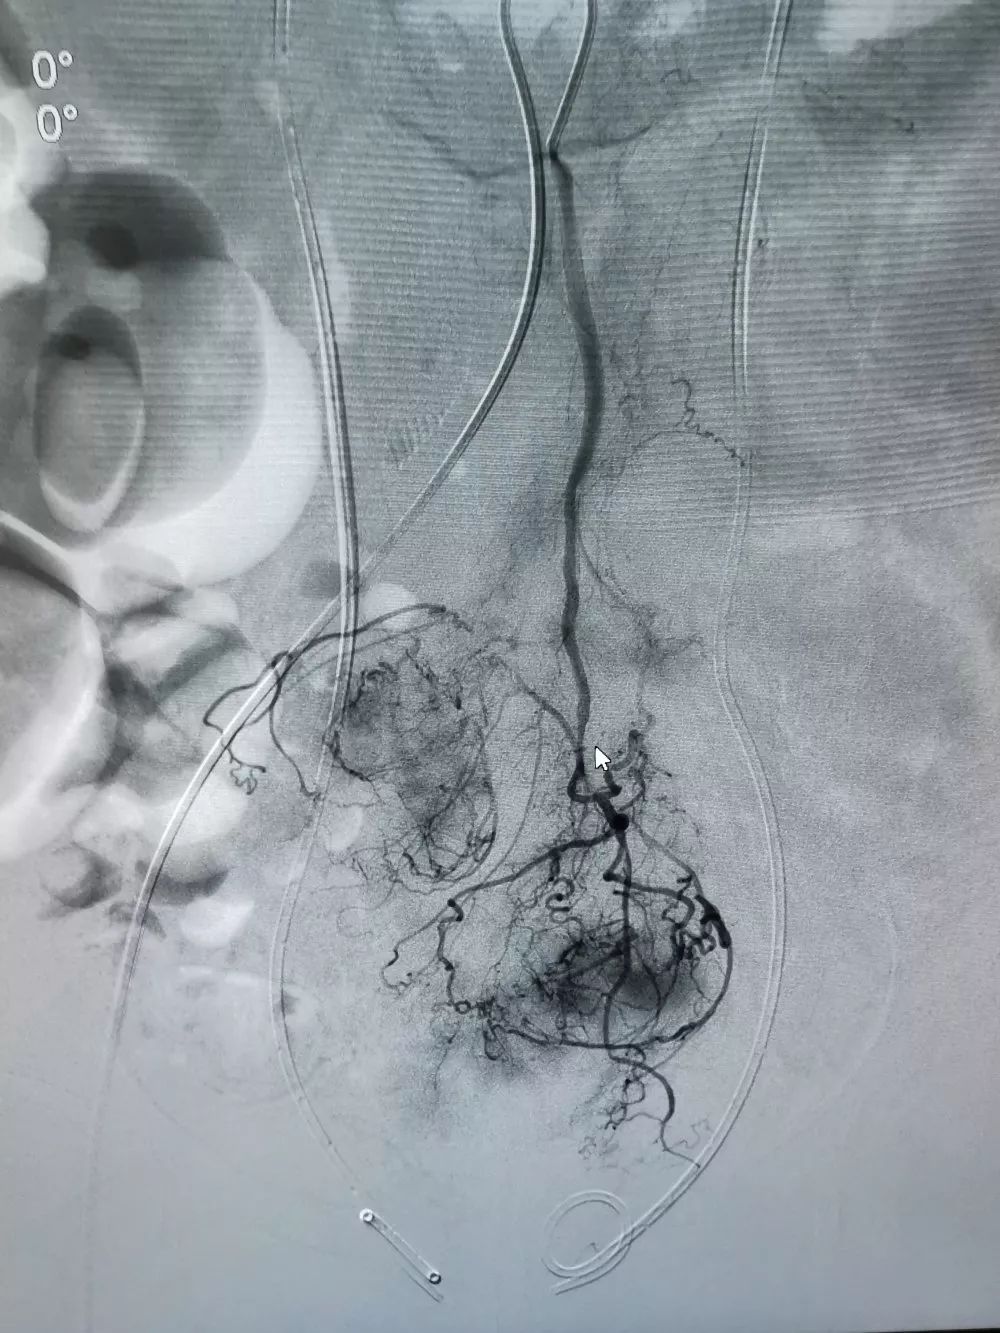

肠系膜动脉造影如图

图片尺寸2000x2667